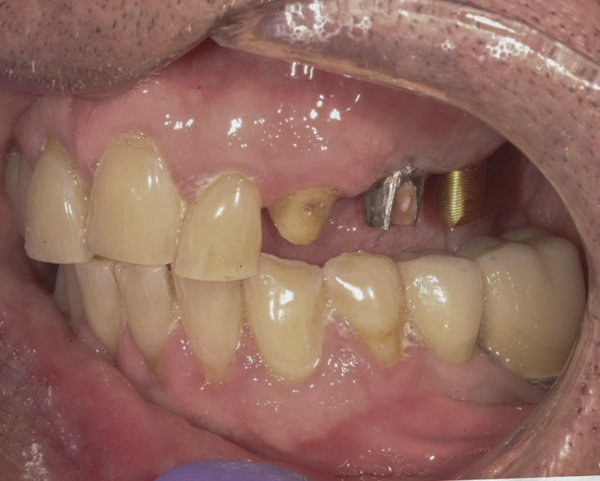

Background: The patient in this case presented with a failing dentition due to generalized severe periodontal disease with secondary endodontic lesions. She adamantly refused to wear removable transitional prostheses. Full maxillary and mandibular extractions were performed in the first phase of treatment. Not all implants could be placed in this initial phase due to the need for healing of certain grafted sites. The implants placed in this first phase were loaded with conical abutments and, in some cases, their angulated counterparts (Figure 16 and Figure 17). These stock titanium abutments were selected to avoid the need, as in Case 3, to change or remill the more costly custom abutments. They also have the advantage of making it unnecessary to use temporary cement near and around surgical sites, as they use occlusal screws only for retention.

Results: Stock titanium abutments were used until all tissue healing was achieved and the secondary implants had healed. Figure 18 shows the maxillary and mandibular custom abutments inserted. Figure 19 shows a close-up of the patient’s right side quadrants, depicting the final case 15 months after initial treatment began. Recession can be seen around units corresponding to teeth Nos. 5 and 6. In this case, the authors attempted to minimize recession susceptibility by employing stock temporary screw-retained abutments during healing phases throughout the initial stages of the treatment plan. Despite these efforts, recession still occurred in certain areas where the implants were labially placed. Since the photographs shown in this case were taken, an unsuccessful attempt was made by the patient’s surgeon to graft soft tissue around these sites with recession.

Quantity of buccal bone—Le and Borzabadi-Farahani concluded that a minimum of 2 mm of facial bone is necessary to prevent future recession.23 Bashutski and Wang noted that the most common esthetic complication is gingival recession, and cited inadequate buccal bone thickness, implants placed too far buccally, and failure to graft “jumping distance” during immediate placement in the etiology of recession.22 Case 5’s final result (Figure 19) shows more than 2 mm of labial recession around the implant-supported abutments at sites Nos. 5 and 6 (this was also the case at sites Nos. 13 and 14). Referring back to Figure 17, it is apparent that sites Nos. 5, 6, 8, and 12 demonstrate very little buccal soft tissue due to the labial placement of the implants. Butler and Kinzer support the premise that there must be adequate bone volume facially, even when the implant is placed ideally, and they found that many complications are related more to the implant position and the associated anatomical findings.21

Buccal-labial position of implants—Saadoun and Touati concluded that the buccal orientation of the implant will impinge upon the buccal cortical wall and induce bone resorption and apical migration of the tissue.13 Chu et al reported that if the implant is not placed more palatally and 3-mm to 4-mm apical to the free gingival margin to assure the proper emergence profile, the esthetic outcome may be compromised.34 Bengazi et al’s 2-year longitudinal study demonstrated that anteriorly positioned implants demonstrated slightly more recession than implants in posterior positions.17 Buccal implant placement can be clearly seen in Case 5 (Figure 17) with healing abutments in place.

Proximity to adjacent implants—Tarnow et al24 and Tarnow et al25 recommend that a minimum of 3 mm of bone exist between two adjacent implants. In sites Nos. 13 and 14 (Case 5) the fixture heads have less than 2 mm between them, and the abutments have less than 1 mm (Figure 17). Because interdental tissues do not have the same level of support between implants as they do with natural teeth, interdental distance becomes more critical in predicting the final soft-tissue position.

Figure 16 First-phase implants loaded with conical abutments and, in some cases, their angulated counterparts.

Figure 16

Figure 17 First-phase implants loaded with conical abutments and, in some cases, their angulated counterparts.

Figure 17